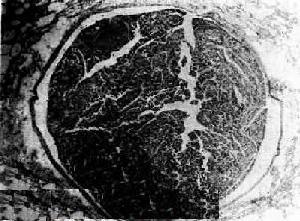

栓子運行途徑1.糾正休克,補充有效循環血容量 休克可誘發和加重脂栓征的發生和發展,必須儘早糾正。在休克沒有完全糾正之前,應妥善固定骨折的傷肢,切忌進行骨折的整復。否則不但會加重休克,而且將誘發或加重脂栓征的發生。在輸液和輸血的質和量上須時刻注意避免引起肺水腫的發生,應在血流動力學穩定後,早期達到出入時的平衡。